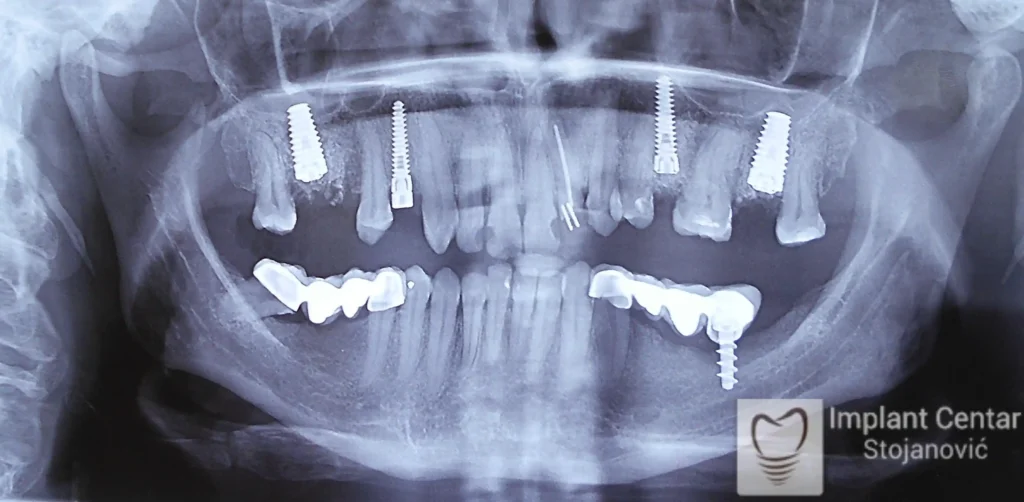

Na slici 1. i slici 2. prikazan je izgled pacijenta pre početka terapije – klinički i rendgenološki.

Nakon vađenja zuba, ugrađeni su implantati. Na slici 3 prikazan je ortopan snimak sa ugrđenim implantatima. Tokom perioda osteointegracije, pacijent je bio zbrinut fiksnim privremenim krunicama na implantatima, koje su izrađene samo dva dana nakon hirurške intervencije.